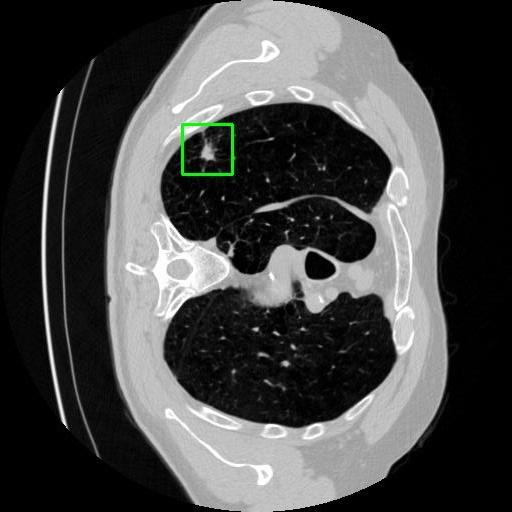

We developed an AI-based system using deep learning models for analyzing lung CT scans to detect and classify pulmonary nodules. We chose the YOLOv11 architecture for its enhanced object detection capability and adapted it specifically for medical imaging, incorporating pixel-level precision and severity classification.

Classification into three severity levels with colored bounding boxes.

Designed a severity classification system that categorizes nodules into null, moderate, and severe using colored bounding boxes, assisting in rapid clinical decision-making.